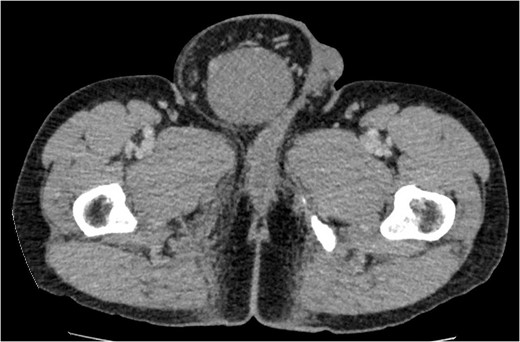

We proceeded with an ultra-sonographic examination of the scrotum, which revealed a heterogeneous mass within the right scrotal sac measuring 7.0 cm × 6.2 cm. The normal right testicle was not seen (Fig. 1). The features were pointing towards a right testicular tumour. Thus, a computed tomographic (CT) scan was ordered, which revealed a right inguinal hernia containing greater omentum and a heterogeneous mass suggestive of a right testicular tumour as seen on the ultrasonography (Figs 2 and 3).

Cross-sectional view of the lower abdomen CT scan revealed a right inguinal hernia containing the greater omentum and a heterogeneous mass.